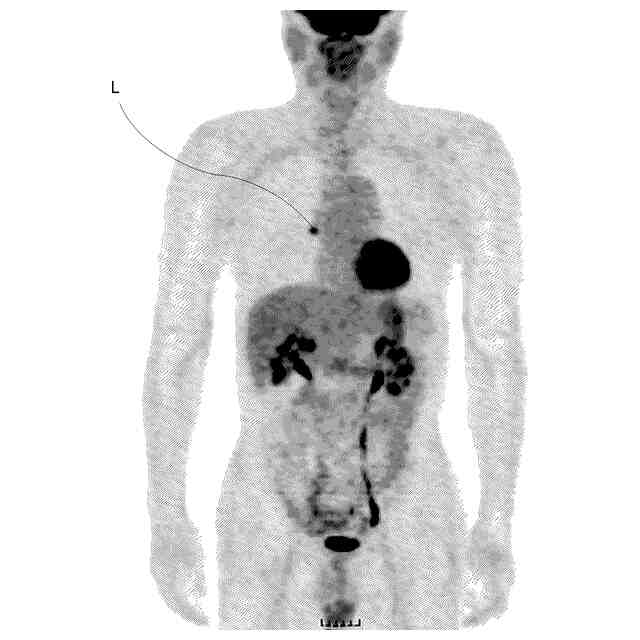

術前にPET装置により撮影した画像の一例を示した図である。